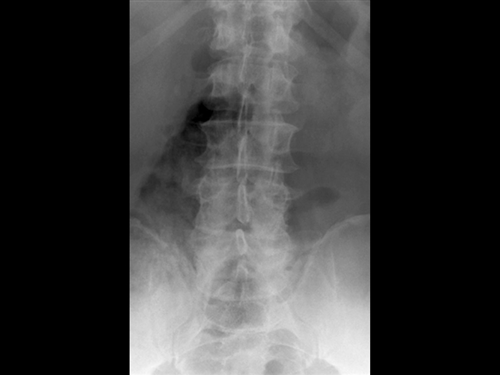

32. You are seeing a 68-year-old female who fell out of her second story apartment window. She complains of severe low back pain and right buttock pain. Her neurologic exam shows she is an ASIA E. Imaging shows a L3 burst fracture with 10 degrees of kyphosis, 30% loss of vertebral body height, and retropulsion of bone with 20% occlusion of the spinal canal. The is no evidence of edema in posterior ligament complex on MRI. What is the most appropriate treatment?

PREFERRED RESPONSE ▼ 2

DISCUSSION: The clinical presentation is consistent with a lumbar burst fracture in a patient who is neurologically intact and has no evidence of radiographic instability. Spinal orthosis and early mobilization is the most appropriate treatment.